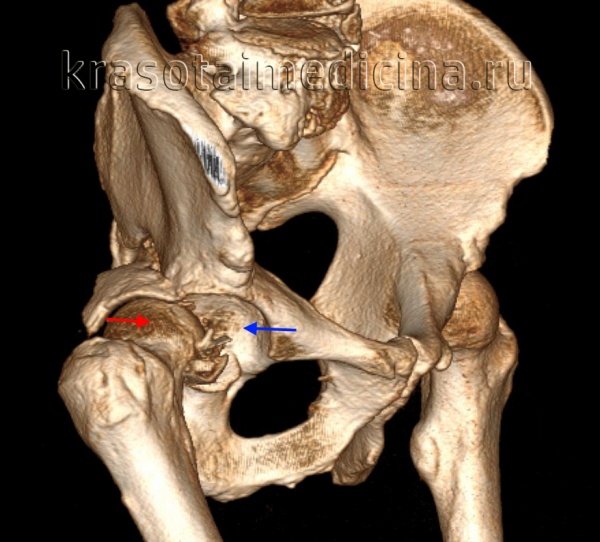

(Слева) КТ в передне-задней проекции, объемная 3D реконструкция: определяется задний вывих головки бедренной кости. КТ выполняется перед закрытой репозицией только если она оказалась неудачной. КТ позволяет оценить положение смещенных осколков, препятствующих репозиции.

КТ таза. 3D-реконструкция. Красная стрелка – вывихнутая головка бедренной кости, синяя стрелка – «пустая» вертлужная впадина.

• Задний вывих:

о Головка бедренной кости располагается позади, обычно немного кверху от вертлужной впадины

о Внутренняя ротация: большой вертел выделен, малый вертел затенен

о Вывихнутая головка бедренной кости выглядит меньше, чем на контрлатеральной стороне вследствие близости к кассете

• Зачастую определяются ассоциированные переломы губы/стенки вертлужной впадины

о Осколок задней стенки обычно треугольный, перекрещивается с головкой бедренной кости в передне-задней проекции